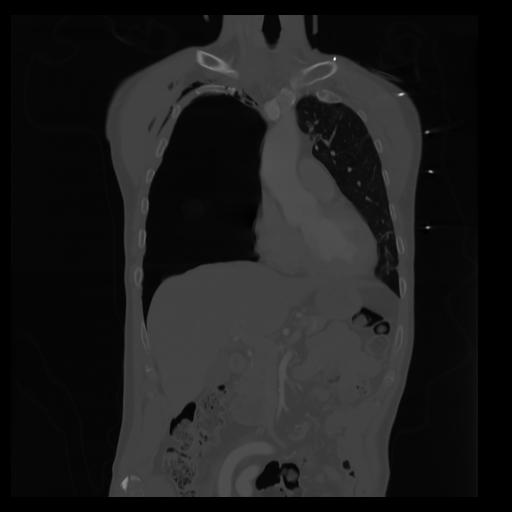

29 CUERPO,CE,Coronal,3.000,CUERPO,Coronal,